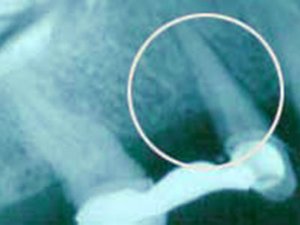

Knochendefekt, entstanden durch Parodontitis

Zustand 1 Jahr nach gesteuerter Geweberegeneration. Der Knocheneinbruch erscheint röntgenologisch wieder aufgefüllt.